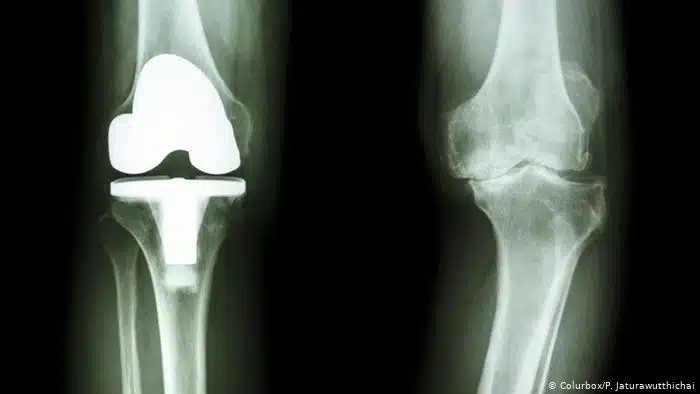

تعد عملية تغيير مفصل الركبة عملية حساسة وضرورية ليتمكن الشخص من استعادة الحركة والرجوع لممارسة أنشطة حياته اليومية بشكل طبيعي، ومن أكثر المفاصل كفاءة وتشتهر بقوتها وجودتها التي تستمر لسنوات طويلة هو مفصل الركبة الأمريكي وذلك لما له من مميزات عديدة، وفي هذا المقال أهم التفاصيل التي توضح ذلك.

يتراوح سعر مفصل الركبة الأمريكي ما بين 100000 إلى 500000 جنيه مصري، والسبب في أنه باهظ الثمن عن باقي أسعار المفاصل هو أنه يتيح للشخص راحة ومرونة أكبر في الحركة.

كما تهتم الشركة المصنعة للمفصل الأمريكي بالجودة والكفاءة في التصنيع وهذا يجعلها الرائدة في المجال مقارنة بالشركات الأخرى التي تصنع بغرض تنافسي دون الاهتمام بالجودة.

أنواع مفصل الركبة الصناعية

أوضح الدكتور عمرو أمل استشاري جراحة العظام والمفاصل والعمود الفقري أنواع مفصل الركبة الصناعية وسنشرحها فيما يلي:

- مفصل من المعدن والبلاستيك: ويكون من أكثر أنواع مفاصل الركبة شيوعا والأقل من ناحية السعر كما ليس له أي مضاعفات على الجسم ولكن الجهاز المناعي لا يتجاوب معه وهذا يهدد نجاح العملية.

- مفصل السيراميك على البلاستيك: يعتبر هذا النوع من المفصل آمن لمن يعاني من الحساسية من المعادن ويكون الجزء الذي يركب في الفخذ هو المصنوع من السيراميك.

- مفصل سيراميك على سيراميك: يعتبر آمن على الأشخاص ولكن له عيب وحيد وهو أنه يصدر أصوات عند الحركة.

- مفصل معدن على معدن: يعتبر الأقل استخدام وذلك بسبب المخاوف من تسرب مادة المعدن إلى الدم مما يتسبب في مخاطر على المدى الطويل.